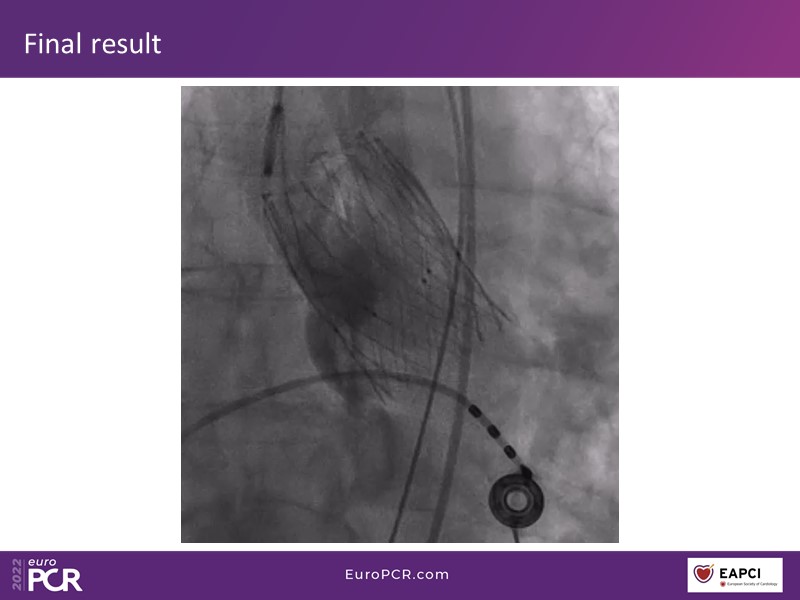

Through the presentation of real-life clinical cases, this session will allow you to discover the use of ALLEGRA for valve-in-valve TAVI, understand the management of coronary artery disease in TAVI patients, better detect when and how to protect coronary arteries during TAVI, or even learn how to perform commissural alignment with ALLEGRA.

- To understand the management of coronary artery disease in patients undergoing TAVI

- To better detect when and how to protect the coronary arteries during TAVI